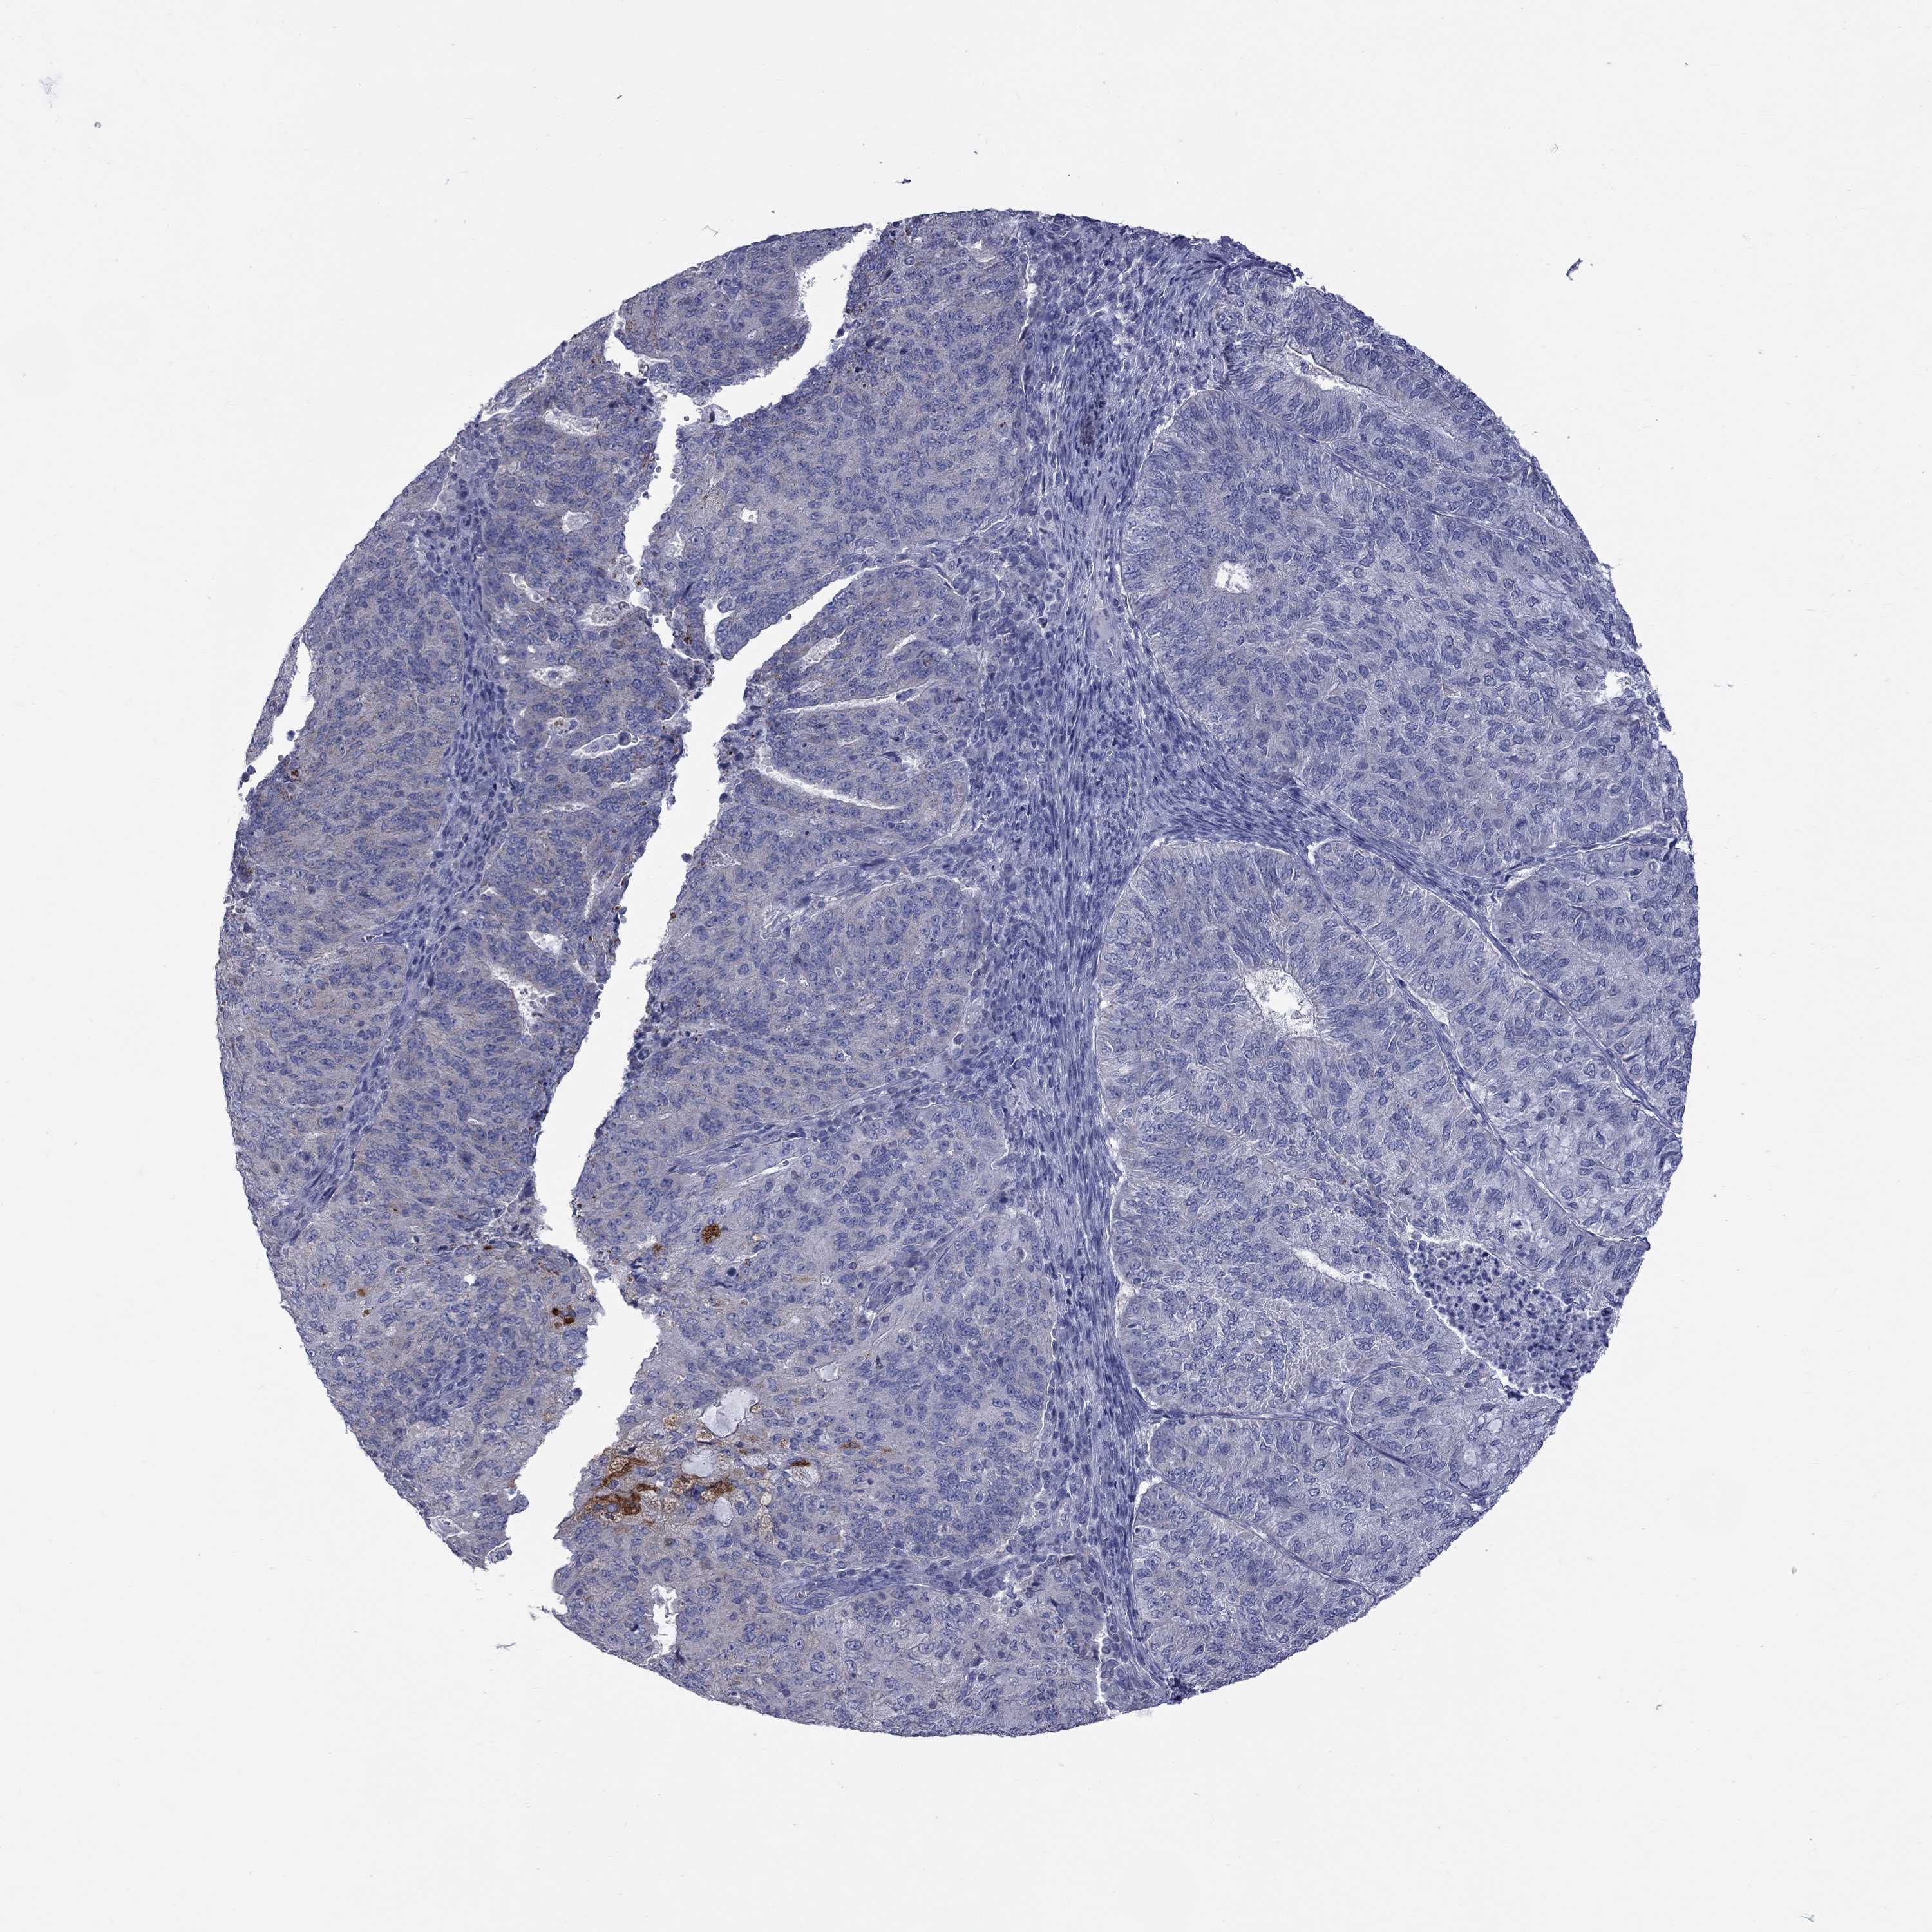

ENDOMETRIAL CANCER - Protein expressioni

A mouse-over function shows sample information and annotation data. Click on an image to view it in a full screen mode. Samples can be filtered based on level of antibody staining by selecting one or several of the following categories: high, medium, low and not detected. The assay and annotation is described here.

Note that samples used for immunohistochemistry by the Human Protein Atlas do not correspond to samples in the TCGA dataset.

Antibody stainingi

Antibody staining in the annotated cell types in the current human tissue is reported as not detected, low, medium, or high, based on conventional immunohistochemistry profiling in selected tissues. This score is based on the combination of the staining intensity and fraction of stained cells.

Each image is clickable and will lead to virtual microscopy that enables deeper exploration of all samples and also displays staining intensity scores, fraction scores and subcellular localization as well as patient and tissue information for each sample.

Antibody HPA049395

Antibody HPA053288

Staining

High

Medium

Low

Not detected

Intensity

Strong

Moderate

Weak

Negative

Quantity

>75%

75%-25%

<25%

None

Location

Nuclear

Cytoplasmic/membranous

Cytoplasmic/membranous,nuclear

Adenocarcinoma, NOS

Carcinoma, NOS